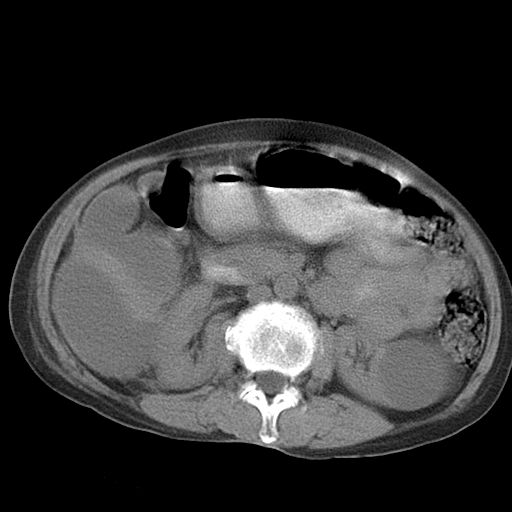

以下是引用dyqct在2006-12-7 21:08:00的发言:[br]考虑:1、肝内外胆管多发性结石伴肝左叶外侧段肝萎缩;[br] 2、右膈下多发脓肿;[br] 3、右侧少量胸腔积液、斜裂积液;[br] 4、左肾囊肿。

以下是引用jiazh在2006-12-7 20:37:00的发言:[br]肝脏周围半狐形低密度影,肝脏表面受压推移,考虑膈下脓肿可能性大;2、右侧胸腔积液

以下是引用拾荒者在2006-12-7 21:44:00的发言:[br]肝内外胆管多发结石,右膈下多发脓肿,右胸膜腔及叶间裂积液,左肾囊肿。[br] [br]